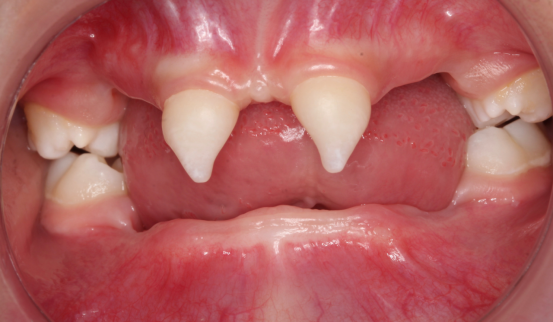

患者4岁,乳牙未正常萌出,上颌仅4下颌仅2颗乳牙,不能正常咀嚼,于2022年底在外地就诊多次无法修复,专程到口腔医院就诊。在后疫情时期,患者经王永门诊诊治后商讨出诊疗方案医院细心安排,于222由王永带领谭雯珈、姜炜鹏等医师,使用修复、正畸、修复工艺等多项技术,顺利完成了大面积乳牙缺失修复患儿现场进食效果良好,家长及患儿十分满意。

因其口腔表征为先天缺牙甚至无牙颌,且缺牙患儿口内余留牙往往表现为锥形牙、釉质发育不良、牙槽嵴发育不良等,可严重影响患儿的咀嚼功能及面部软硬组织生长发育。

(2) 牙弓较小,常规人工牙无法完成排牙;

(3) 牙体形态发育异常,常规卡环固位力差。